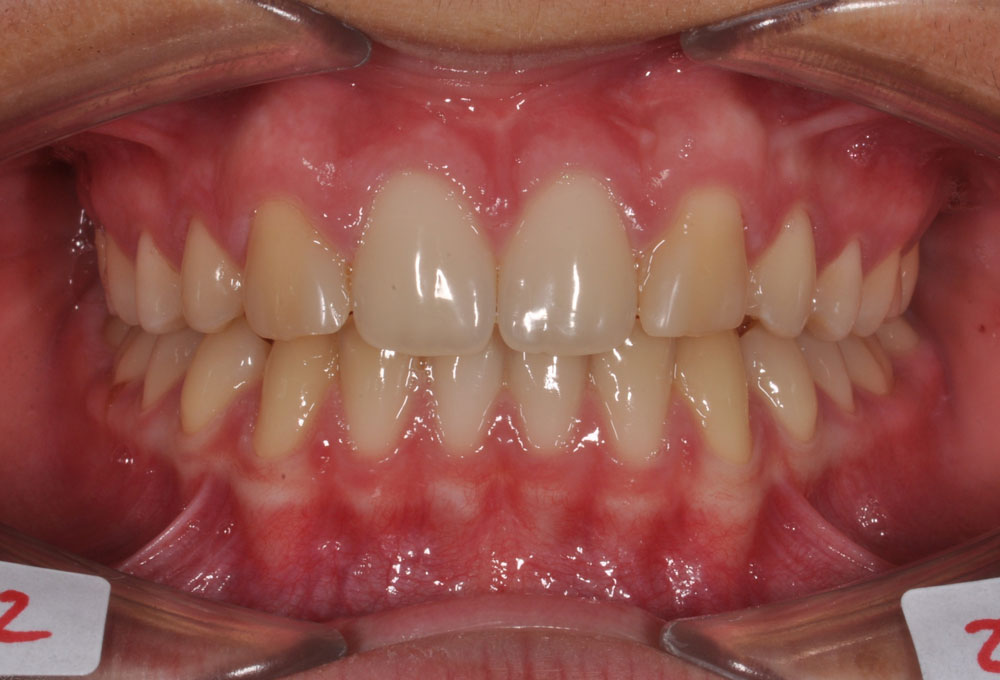

Il vantaggio principale di questa soluzione è che si può ottenere una buona estetica del sorriso e una corretta funzione masticatoria senza ricorrere a sostituzioni protesiche.

Frequentemente, in questi casi si ricorrere a una finalizzazione estetica con rimodellamento della forma di alcuni elementi dentali (camouflage), per meglio inserirli nel contesto estetico e funzionale orale.